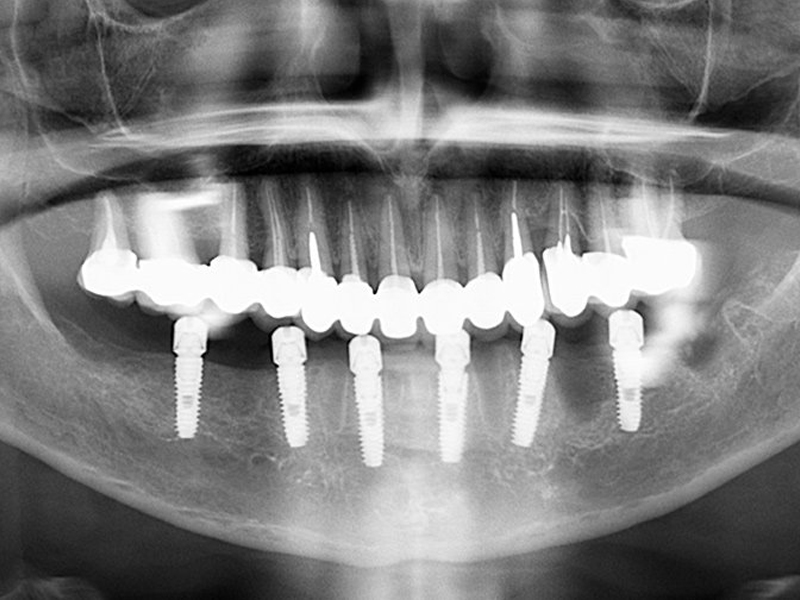

• This operation is carried out after the panoramic and CT scan of the patient's dental arches;

Performed treatments